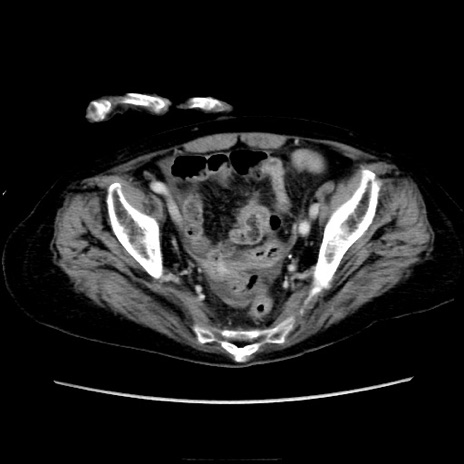

横断像